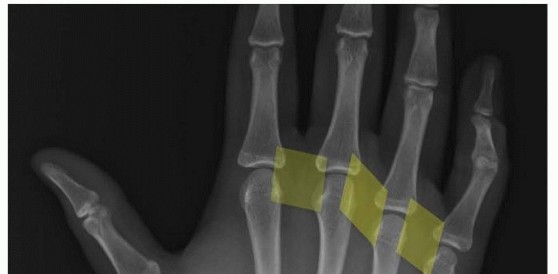

Arthroscopic Reduction and Fixation of Distal Radius and Ulnar Styloid Fractures